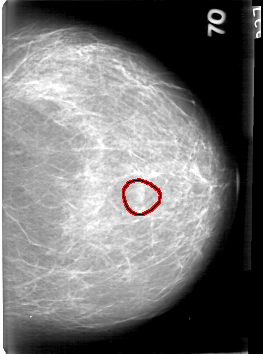

D_4086_1.LEFT_CC

FILE: D_4086_1.LEFT_CC.OVERLAY

TOTAL_ABNORMALITIES 1

ABNORMALITY 1

LESION_TYPE MASS SHAPE OVAL MARGINS OBSCURED

ASSESSMENT 0

SUBTLETY 4

PATHOLOGY BENIGN

TOTAL_OUTLINES 1

BOUNDARY